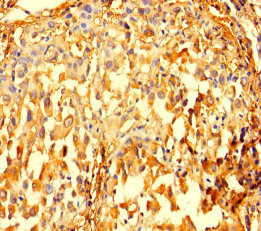

Immunohistochemistry of paraffin-embedded human lung cancer using CSB-PA01195A0Rb at dilution of 1:100